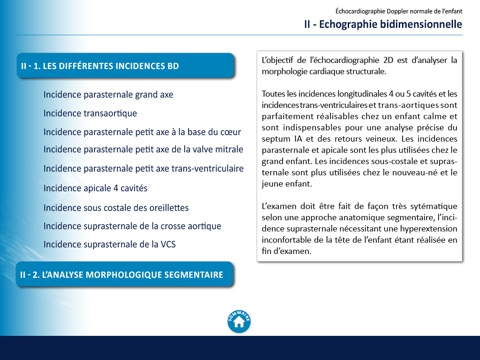

Echocardiographie chez l'enfant

Abord de léchocardiographie Doppler chez lenfant dans son aspect normal mais aussi pathologique (CIV, Transposition des gros vaisseaux, CIA, Persistance du canal artériel, HTAP, Obstacles du cœur gauche), sous légide de la Filiale de Cardiologie Pédiatrique Congénitale de la Société Française de Cardiologie.